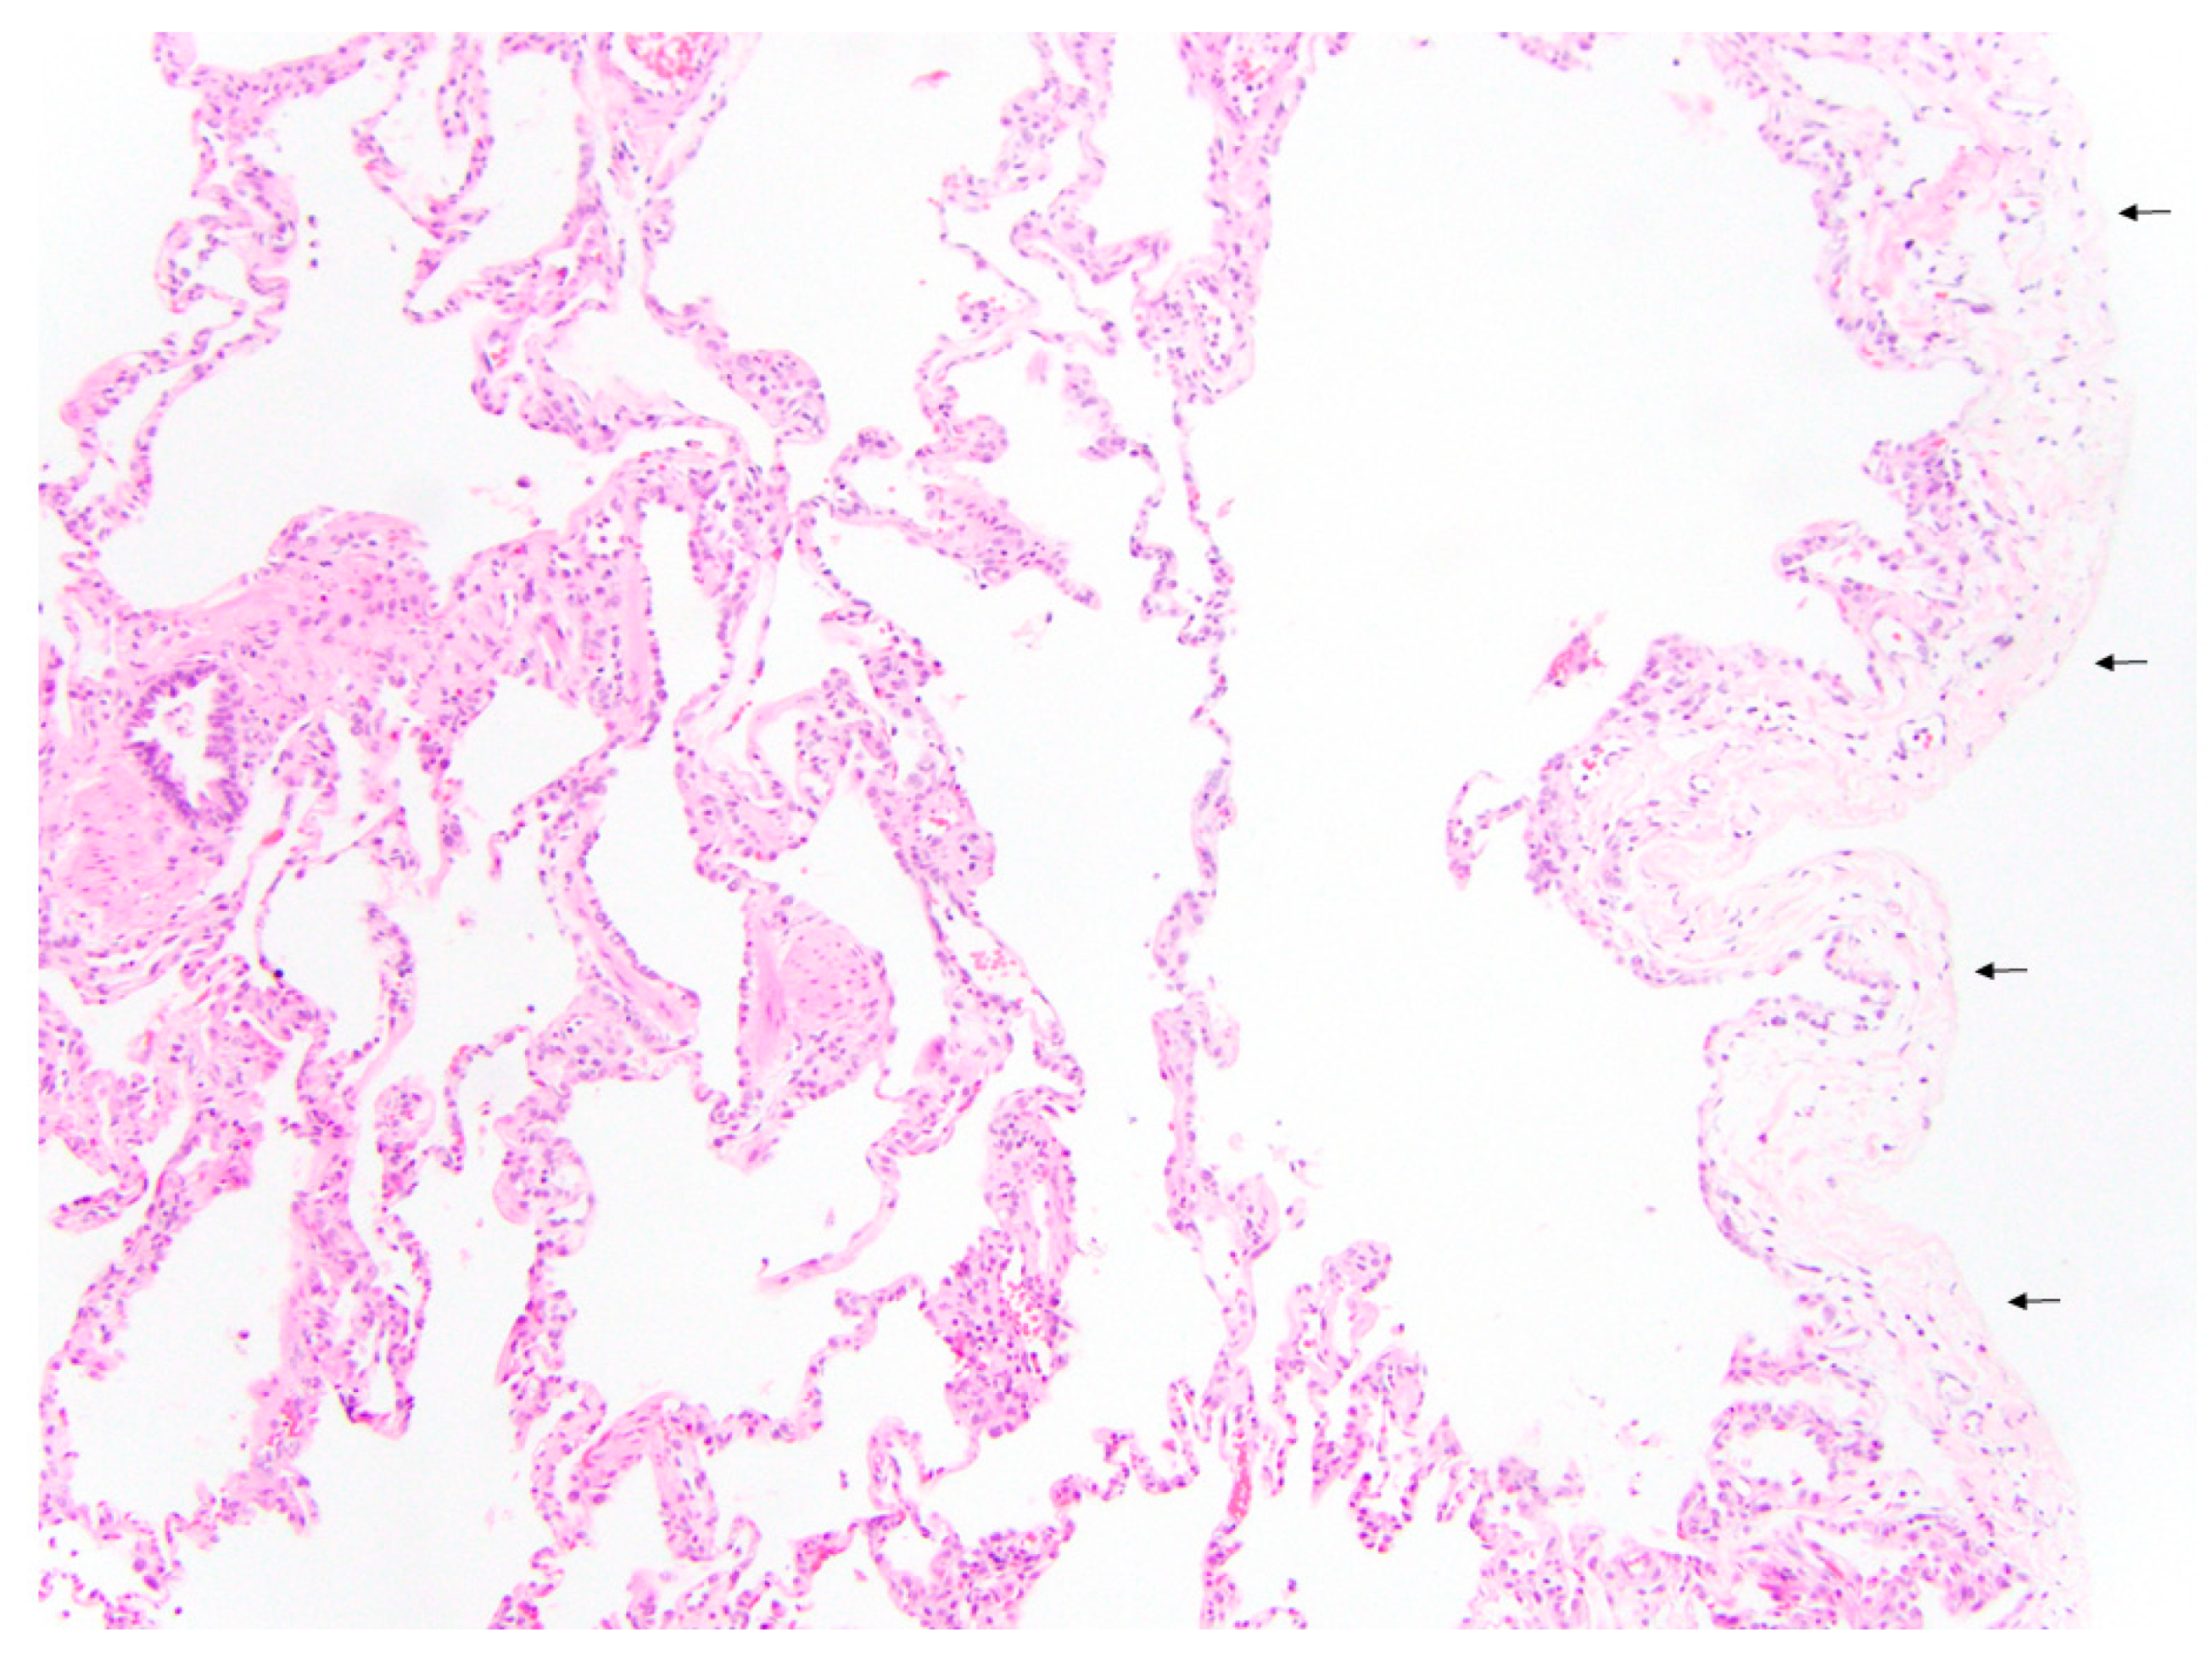

- Pogoriler, J.E.; Kulik, T.J.; Casey, A.M.; Baird, C.W.; Mullen, M.P.; Jenkins, K.J.; Vargas, S.O. Lung Pathology in Pediatric Pulmonary Vein Stenosis. Pediatr. Dev. Pathol. 2016, 19, 219–229. [Google Scholar] [CrossRef]

| Septal Thickening | 39/49 (76%) | 0/54 (0%) | <0.001 |